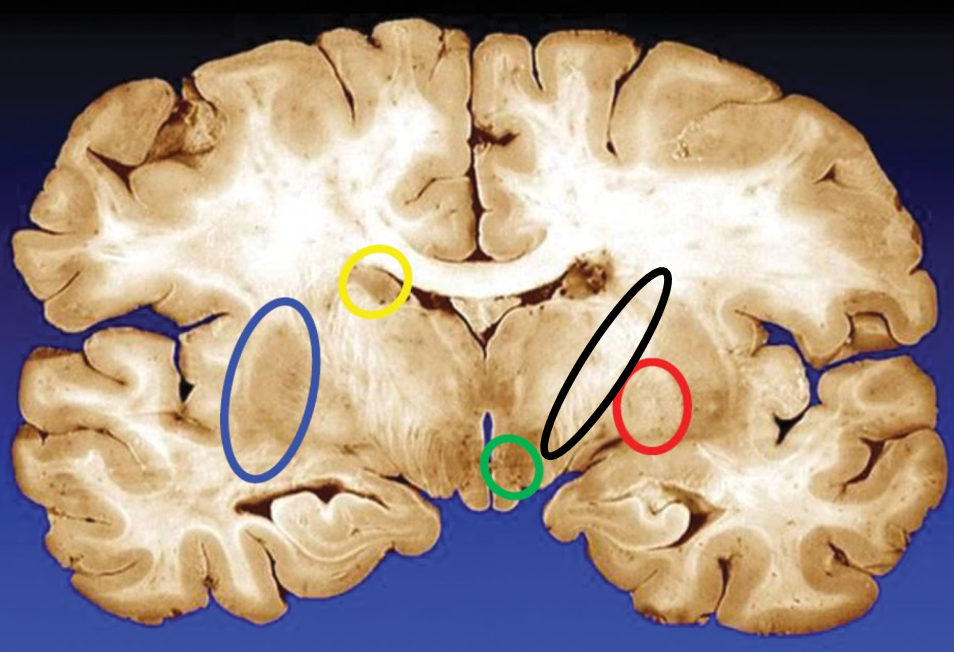

blue

putamen

yellow

caudate

green

subthalamic nuclei

black

internal capsule

red

globus pallidus

name the condition

Huntington’s (reduced caudate)